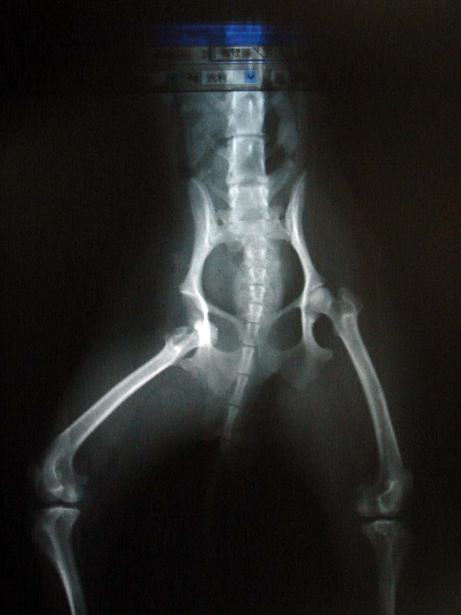

另個方法我不知道大型狗是否適合,我現在養的小型狗體重1.8公斤

有一天,從床上跳下髖骨嚴重脫出去了,無法走路...只能用跳的

醫生提議,把髖骨(股骨頭)拒掉,偏離的骨頭才會回到原位,狗才能走路

我問:那拒掉的髖骨(股骨頭)位子,就沒有骨頭~空空的耶~那怎麼辦?

獸醫:不用擔心,肌肉會長入髖臼部分填補,術後復健後狗兒依然可跑跳

而擔心的我,手術成功了!

手術16000+住院N天,共花2萬元

這個方法我不知道適不適合大型犬使用(因為小型狗體重少負擔低)